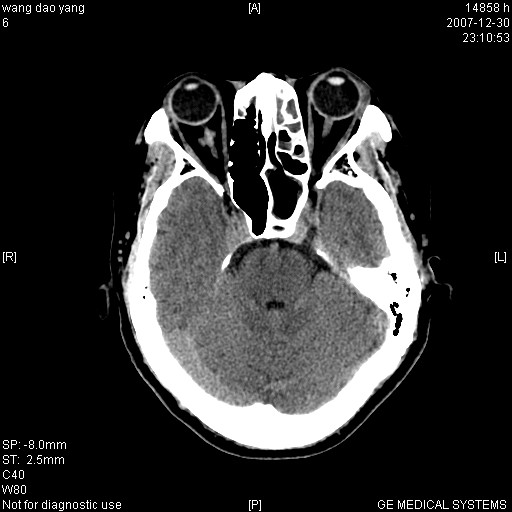

因外伤做ct

1。左侧筛窦蝶窦少量积液,2。右眼眶视神经鞘瘤可能性大,建议增强一下

肌圆锥内占位性病变,血管瘤可能性大。

1 病灶位于肌圆锥内,从第一帧看,和视神经关系不紧密。

2 病灶边界光整,形态欠规则。

3 病灶密度明显高于同层面的正常软组织。

外伤的话首先考虑球后血肿!!

病灶形态不规则,临床有外伤史,支持考虑:球后血肿!!!

考虑右侧视神经脑膜瘤或血管瘤,建议增强进一步检查。

考虑右侧视神经脑膜瘤或视神经胶质瘤,建议增强进一步检查鉴别。

考虑右侧视神经鞘瘤,脑膜瘤或纤维瘤。

球后肌锥内小团块状软组织密度影(性质待定);建议:行ct增强扫描或mri检查。